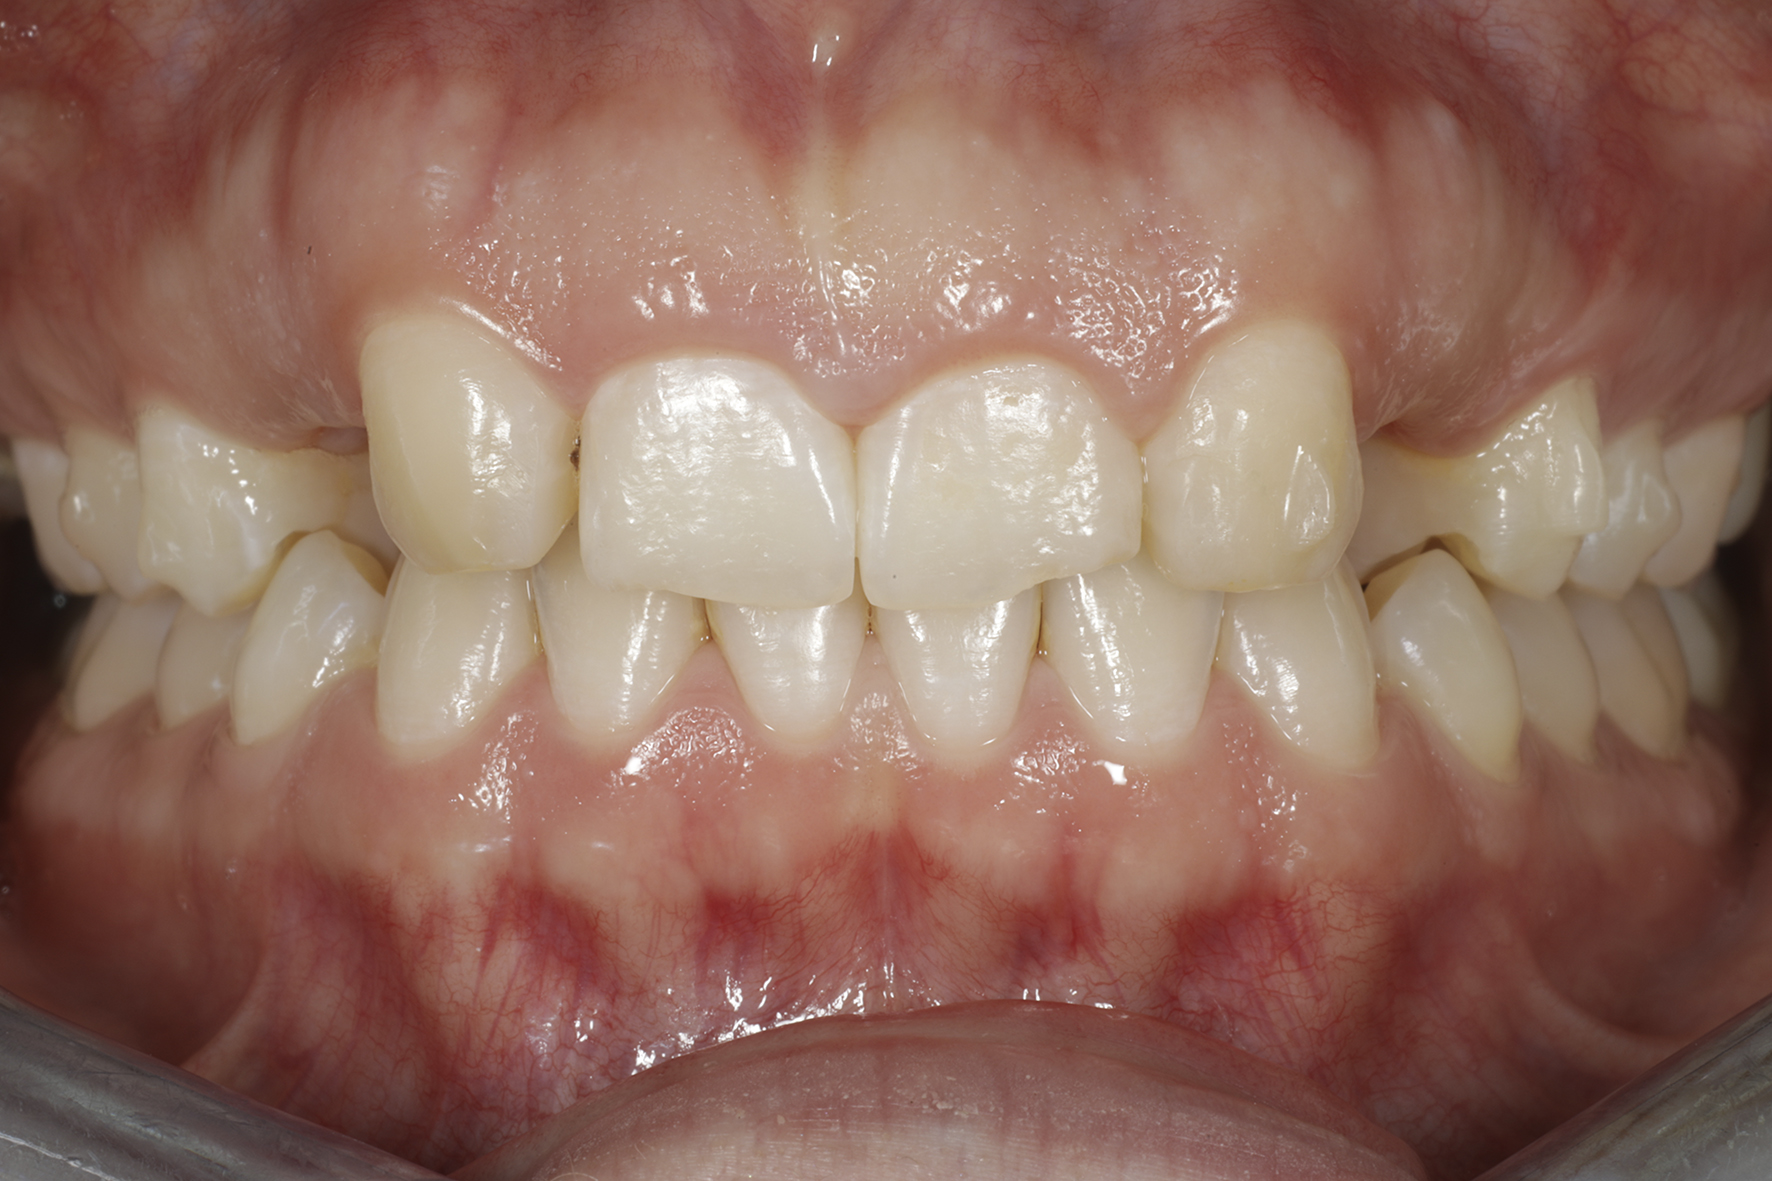

Alkutilanne.

Alkunäkymä huulet retraktoreilla sivuun loitonnettuina.